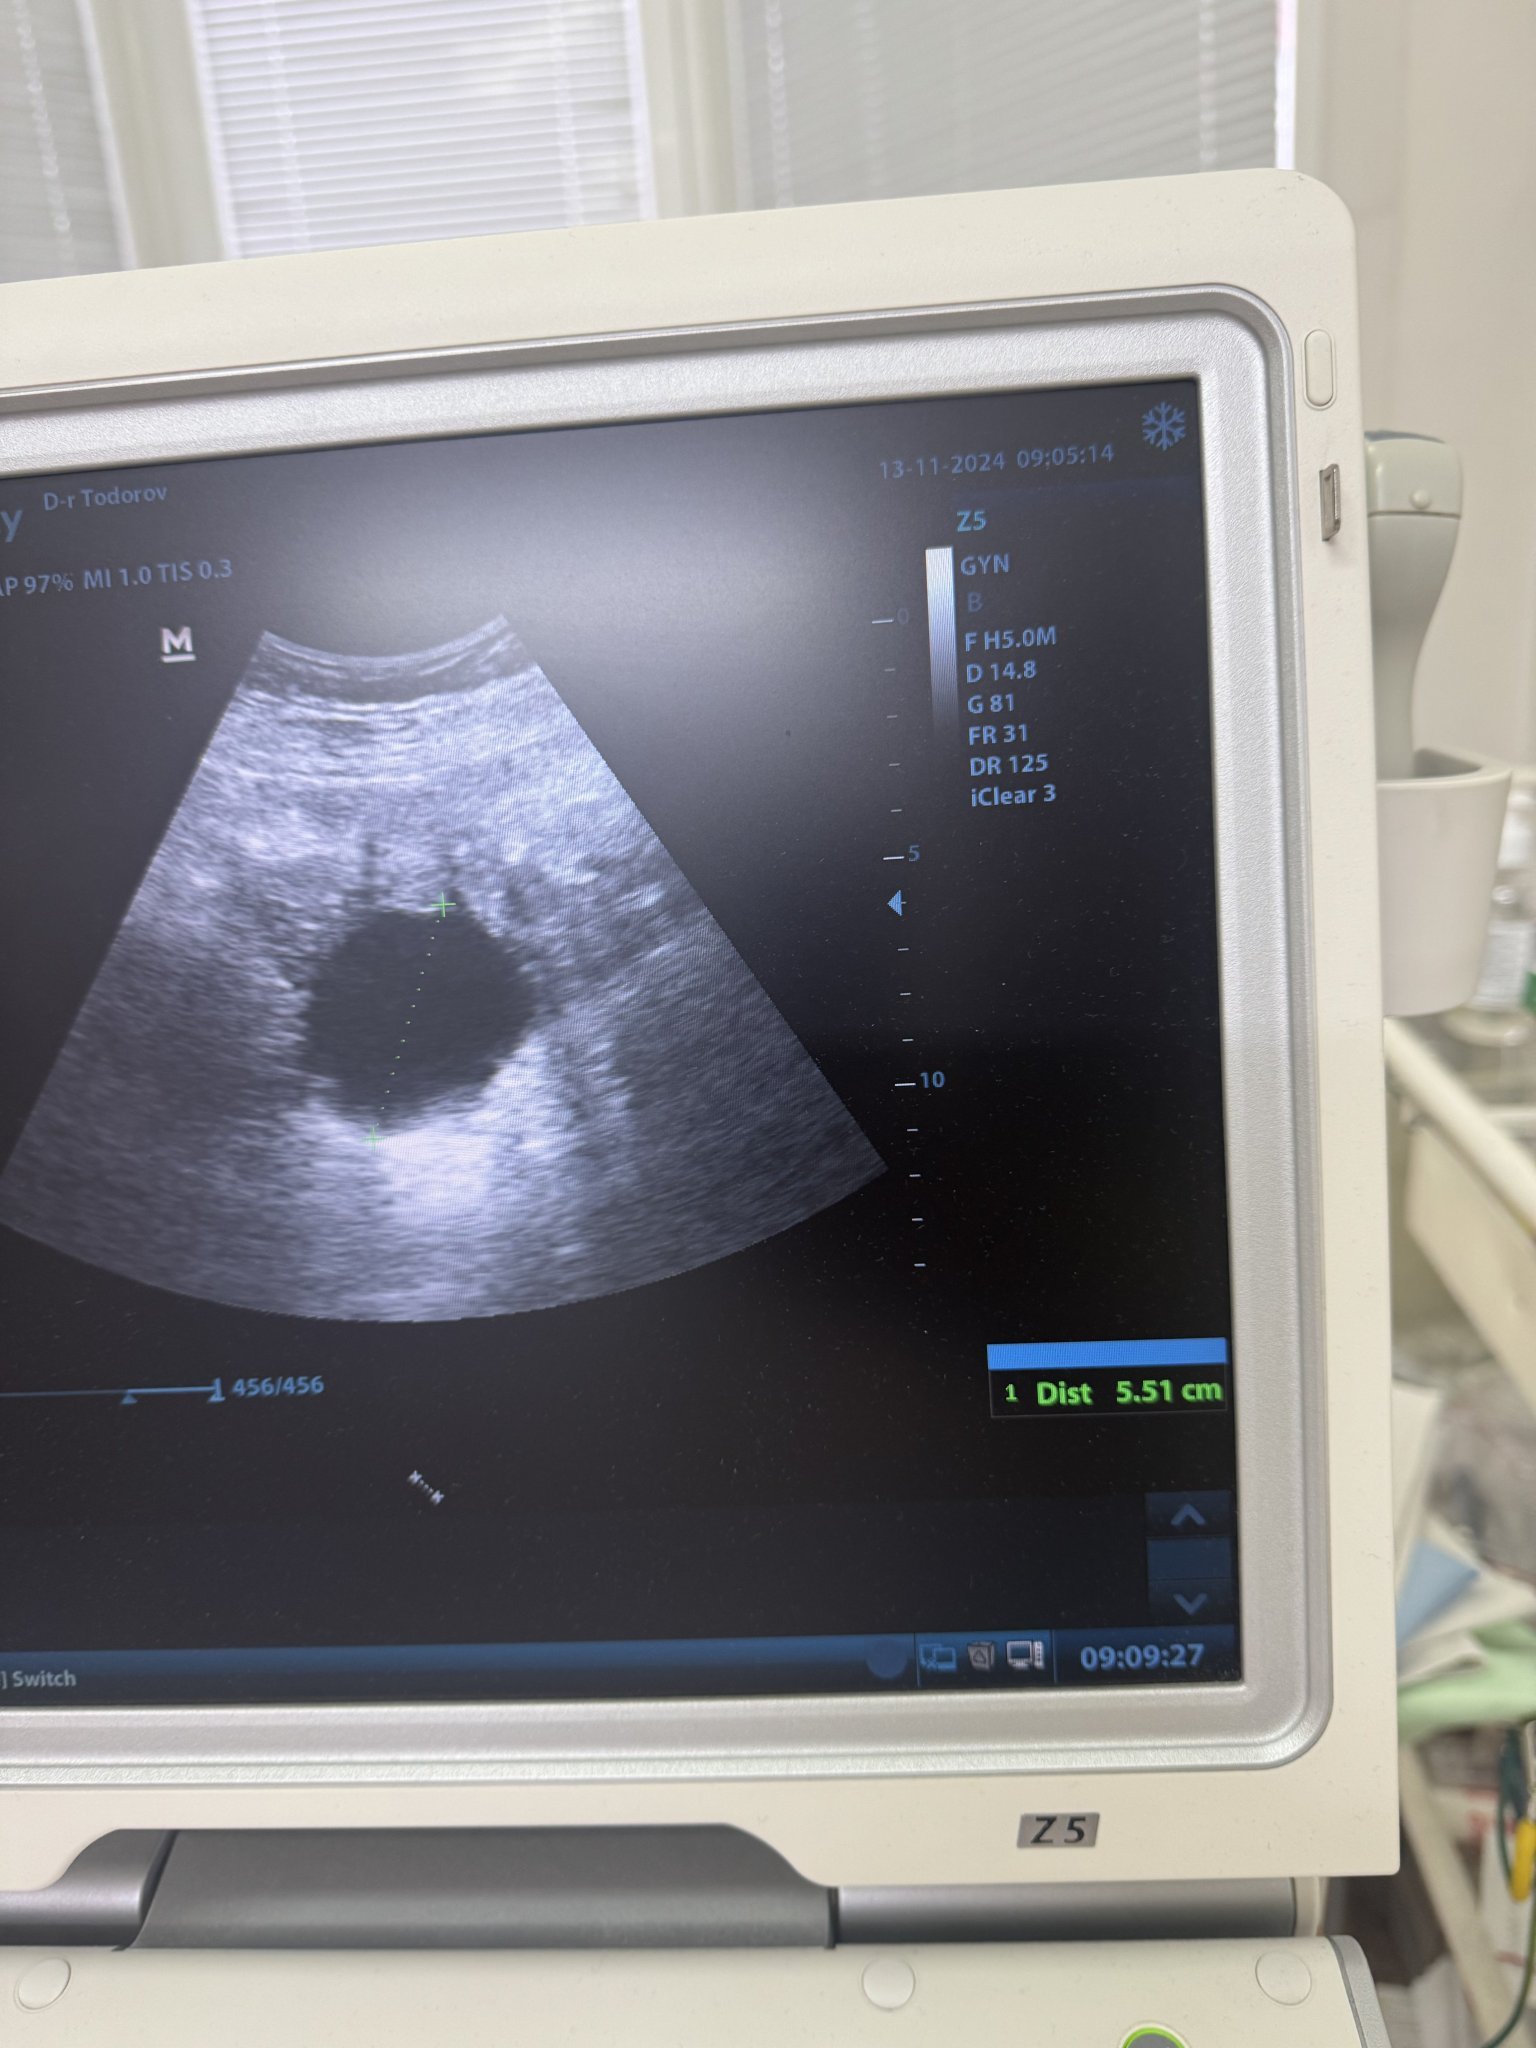

Привет момичета. Бях на гинеколог, гледа ме само на ехо, откри киста 5.5 см, каза, че кървенето не е от нея. Изписа ми дуфастон от неделя, ако не е спряло кървенето, и Ясмин от първия ден като ми дойде цикъла. Твърди, че болките в корема ми, особено в дясната част (където е кистата) не са от нея, но и не даде яснота от къде идва нито те, нито кървенето. Цито ще прави, когато спре кървенето. Аз отново съм в егати филма, защото реално не получих никаква информация от къде е тази болка и това кървене толкова време. Въпросът ми е - вие смятате ли, че е болката може да е от нея? Усилваща, на моменти пронизващата в дясно най-вече. Благодаря отново!

Това черното кръгче ако е кистата, ами че то това е голямо нещо, почти е заела целия яйчник как няма да боли от това? Според мен проблемите са си баш от нея.

Иначе, да - това черното е кистата 5.5 см е, аз не съм добра в сантиметрите, но горе долу мога да предположа, че е с големината на пинг понг топче. Не знам колко са големи яйчниците де… не знам, имала съм кисти, но най-голямата е била 2 см, такова чудо не съм виждала по снимките ми от ехографи. 😞

Ами, разбира се, че болките са от нея. Учудвам се, че лекар би твърдял обратното.

И аз мисля, че вероятно е от нея и даже бих сменила лекаря, този нещо хич не звучи добре. Иначе кистата е голяма, яйчниците са колкото орех принципно.

5 санта киста и се предполага да не я усещаш че е там ли? Че то едно по-дребно яйце е толкова голямо... Отделно че за да я има, явно и друго не е наред, тя няма да се появи от нищото.

Аз се чудя какви лекари са това при 5 см киста да кажат че не е проблем, и че не прави проблеми. Това си е наистина с размерите на едно яйце при размер на яйчника колкото орех, не знам, не знам. 🙉🙉🙆‍♀️🙆‍♀️